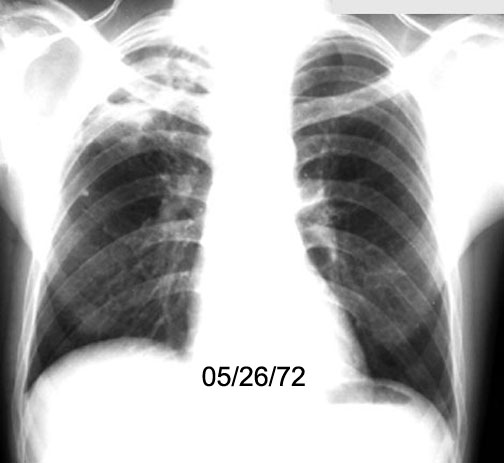

Case 2 Labeled Image What is the differential for multiple cavities?